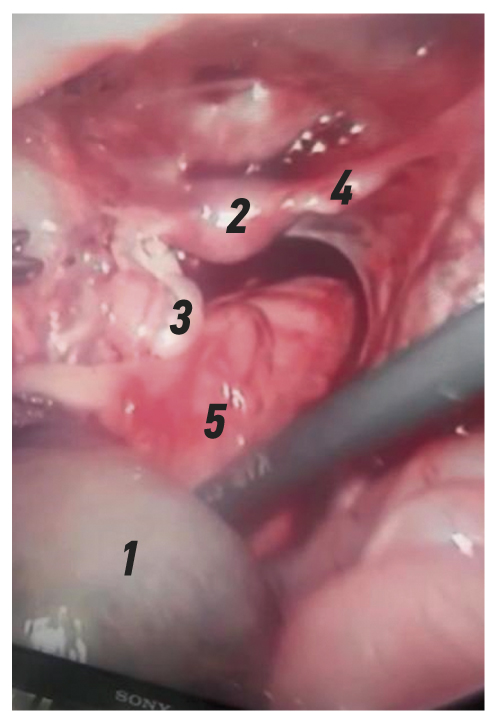

В ходе ультразвукового исследования срединно в малом тазу выявлено образование с жидкостным и паренхиматозным компонентами. Жидкостный компонент размерами 40×31×37 мм, с плотной капсулой (местами с расслоённой стенкой). Внутренний контур капсулы неровный. При цветном допплеровском картировании в капсуле определяются сосуды. В просвете кисты плавающая густая взвесь и гиперэхогенные включения размерами 6,8 мм и 8,4 мм. Паренхиматозный компонент неоднородный с анэхогенными включениями до 7,0 мм, ячеистой структуры. Заключение: объёмное образование в проекции малого таза, дермоидная киста яичника (?) (рис. 1).

Рис. 1. Ультразвуковое исследование органов брюшной полости: стрелкой указана густая взвесь.

Fig. 1. Ultrasound examination of the abdominal organs: an arrow indicates thick suspension.